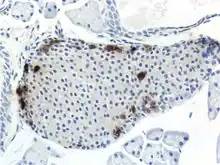

Through different microscopy techniques, the structural related details of PP cells have been able to be better understood. This is inclusive of how big they are, what their cellular membranes look like, the proteins associated with them, and even their size. PP cells are elongated cells. Another one of these details can be noted in insulins secretory granules, or container like buds, that store insulin within a cell. In PP cells, the size of the insulin granules are smaller and spherical and similar to those in alpha cells. This is noted in human PP cells, but different animals have been shown to have different sized granules compared to humans, like rodents. In cats and dogs, PP cells have large granules.[6] In rats, PP cells have few granules, similar to humans. In dogs, some PP cells are located in the walls of the antrum of the stomach.[3]